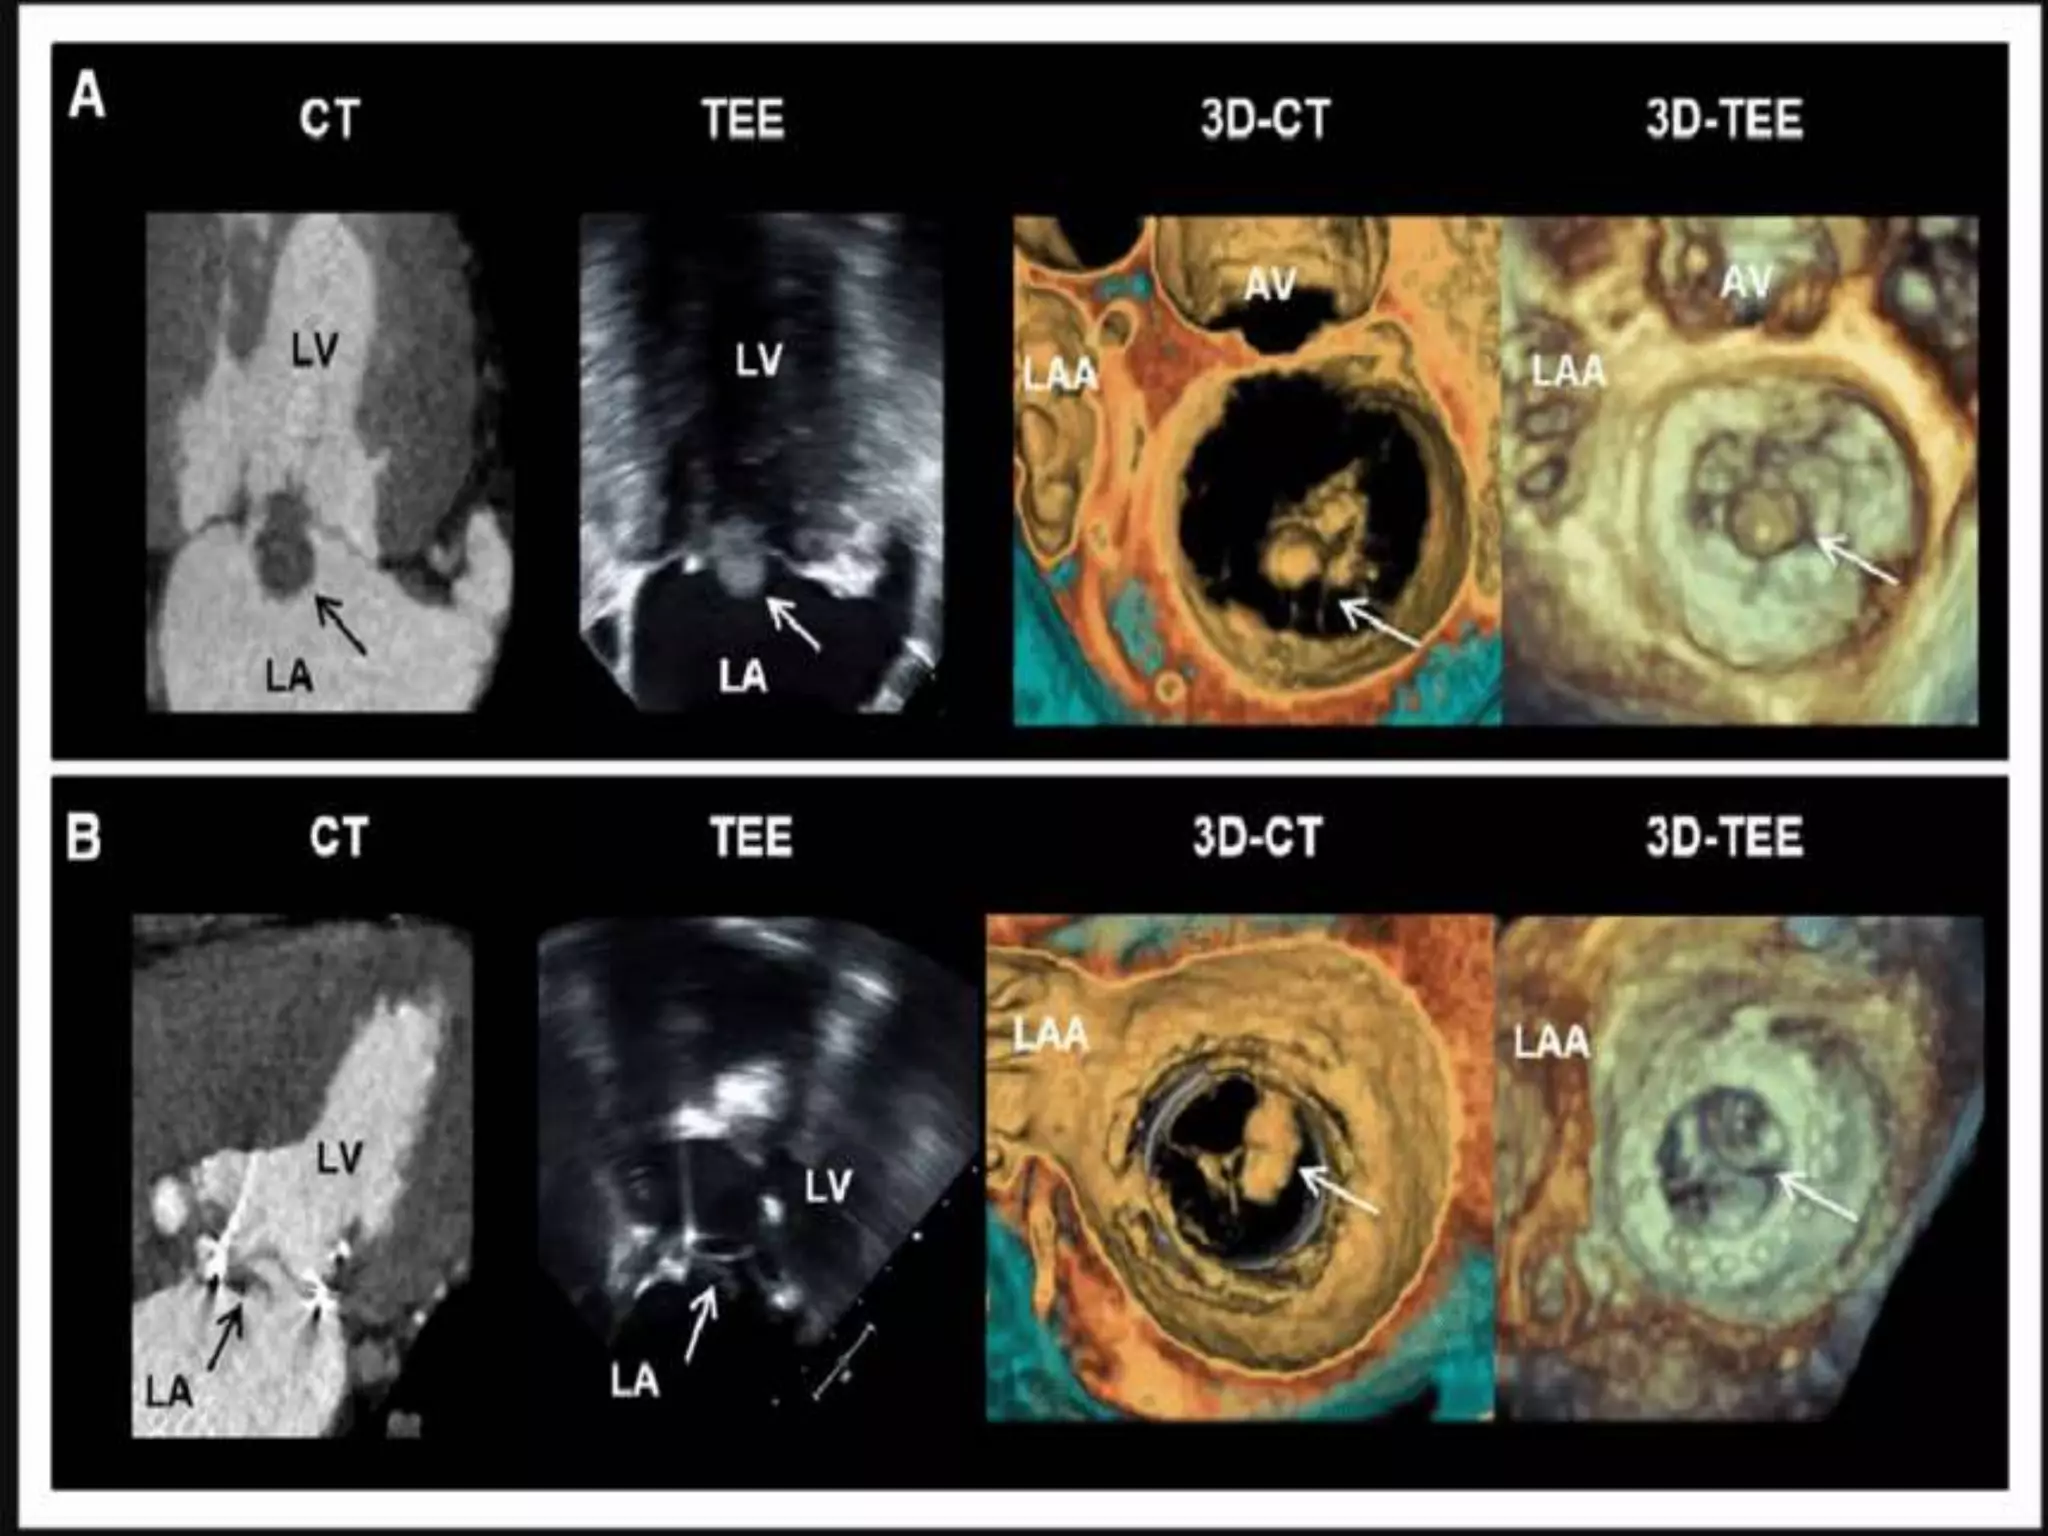

 As discussed, central to the diagnosis of IE being a part of major criteria,

echocardiography

 Hanging oscillating intra cardiac mass attached to valves, supporting structures,

implanted devices or in the path of regurgitant gets (ECHO)

 TTE vs TEE

 Cardiac CT – Strictly speaking, not indicated as per guidelines. Yet useful

 MRI brain

 As discussed,central to the diagnosis of IE being a part of major criteria, echocardiography  Hanging oscillating intra cardiac mass attached to valves, supporting structures, implanted devices or in the path of regurgitant gets (ECHO)  TTE vs TEE  Cardiac CT – Strictly speaking, not indicated as per guidelines. Yet useful  MRI brain